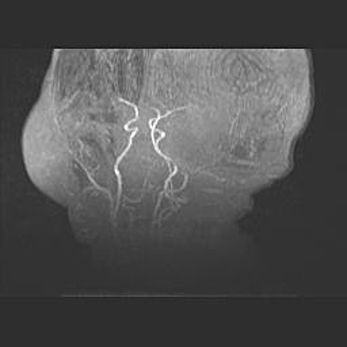

Множественные кисты обоих полушарий головного мозга, наибольшая из них в правой затылочной области. Ассиметричная атрофическая гидроцефалия.

Возраст: 7 месяцев

Вес: 5660 г

Пол: мужской

Окружность головы: 41,5 см

Срок гестации: 28-29 недель

Кисты головного мозга развиваются в результате многоочаговых некрозов вещества мозга и возникают вследствие перенесенной перинатальной инфекции, менингитов, энцефалитов, асфиксии, родовой травмы, расстройств мозгового кровообращения различного генеза. Образованию кист в веществе головного мозга плодов и новорожденных способствуют такие факторы, как высокое содержание в нем воды, недостаточная (или отсутствие) миелинизация и слабая астроглиальная реакция на повреждение.

Кисты могут сочетаться с гидроцефалией и другими поражениями головного мозга.